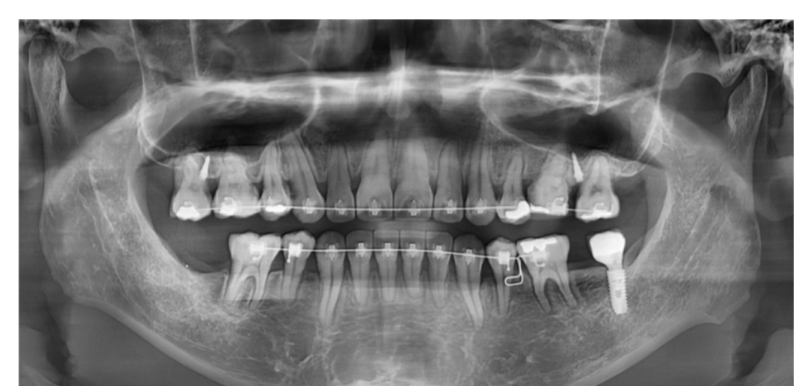

치조골 밀도가 있습니다.

뼈가 단단하신 남성분들의 경우는

치아가 뼈에 딱 달라붙어 있어서 이동속도가 느립니다.

또한 치아 뿌리가 짧은 경우

교정 중 치근 흡수가 발생할 위험이 큽니다.

때문에 교정력(힘)을 약하게 주거나

속도를 늦춰서 안전하게 진행해야 해요.